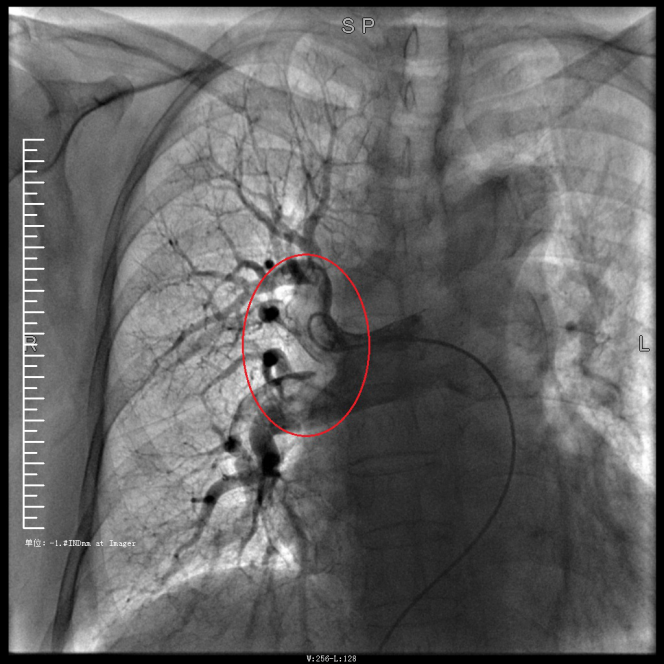

譚婆婆今年已經72歲了,因“突發意識障礙2次”到璧山區人民醫院神經內科治療。譚婆婆沒有基礎心臟病病史,但近段時間活動耐量明顯下降,稍做活動就出現呼吸困難。入院后查BNP及心臟彩超均未提示明顯異常,查D二聚體明顯升高,經心血管內科周波醫師會診后轉入科室繼續治療。在心血管內科主任、內科學(心血管病)博士于長青的指導下,周波醫師成功完成醫院首例“一站式”微創介入手術。在影像中,可以清晰地看到堵塞的血管經溶栓治療后,重新暢通無阻,流動起支撐生命的血液。

肺動脈造影技術是目前診斷肺動脈栓塞的“金標準”,在全程心電監護下,通過股靜脈或者頸內靜脈置入鞘管后,利用導絲引導,將造影導管送入肺動脈;可在左/右肺動脈主干及其左右分支內,分別進行肺動脈造影或選擇性肺動脈造影,存在栓塞的肺動脈血管在造影劑注入后即會顯示出充盈缺損、充盈緩慢、或者血管顯影模糊,嚴重栓塞的肺動脈血管甚至會出現血流截斷征象。

肺動脈導管局部置管溶栓術是通過肺動脈造影確定堵塞的肺動脈部位,然后導管尖端置于血栓處,將尿激酶、鏈激酶或重組組織型纖維蛋白溶酶原激活劑直接注入血栓處,新鮮血栓在足量的溶栓劑作用下溶解。肺動脈內局部用藥特別是小劑量時可減少出血并發癥。

注明:第一張、第二張為術前圖像